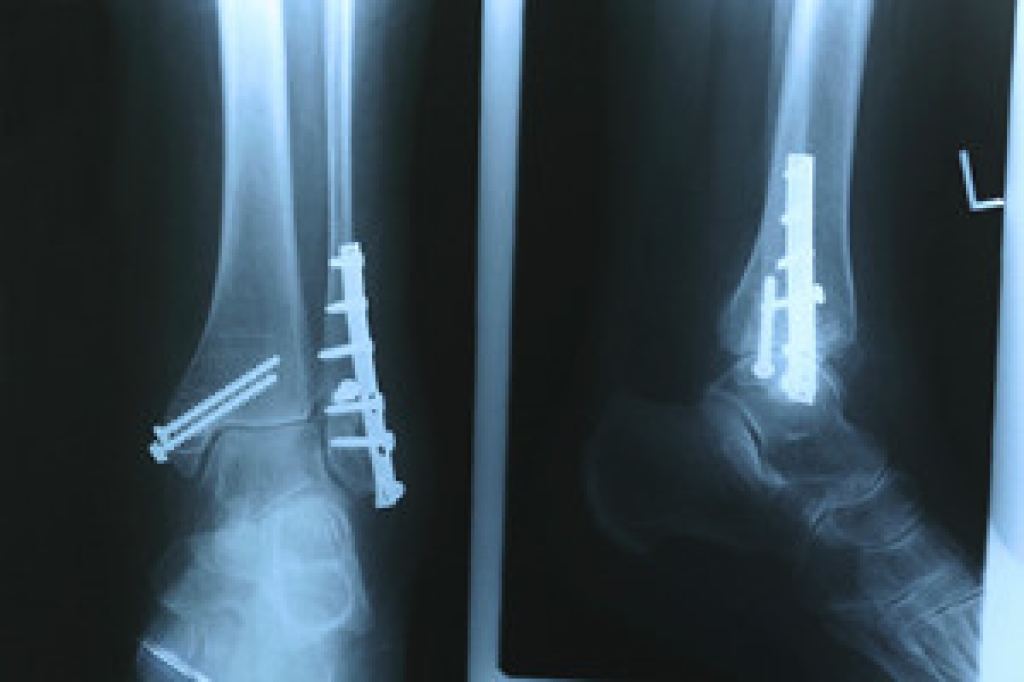

Dealing with Stress Fractures of the Foot and Ankle

Stress fractures occur in the foot and ankle when muscles in these areas weaken from too much or too little use. The feet and ankles then lose support when walking or running from the impact of the ground. Since there is no protection, the bones receive the full impact of each step. Stress on the feet can cause cracks to form in the bones, thus creating stress fractures.

What Are Stress Fractures?